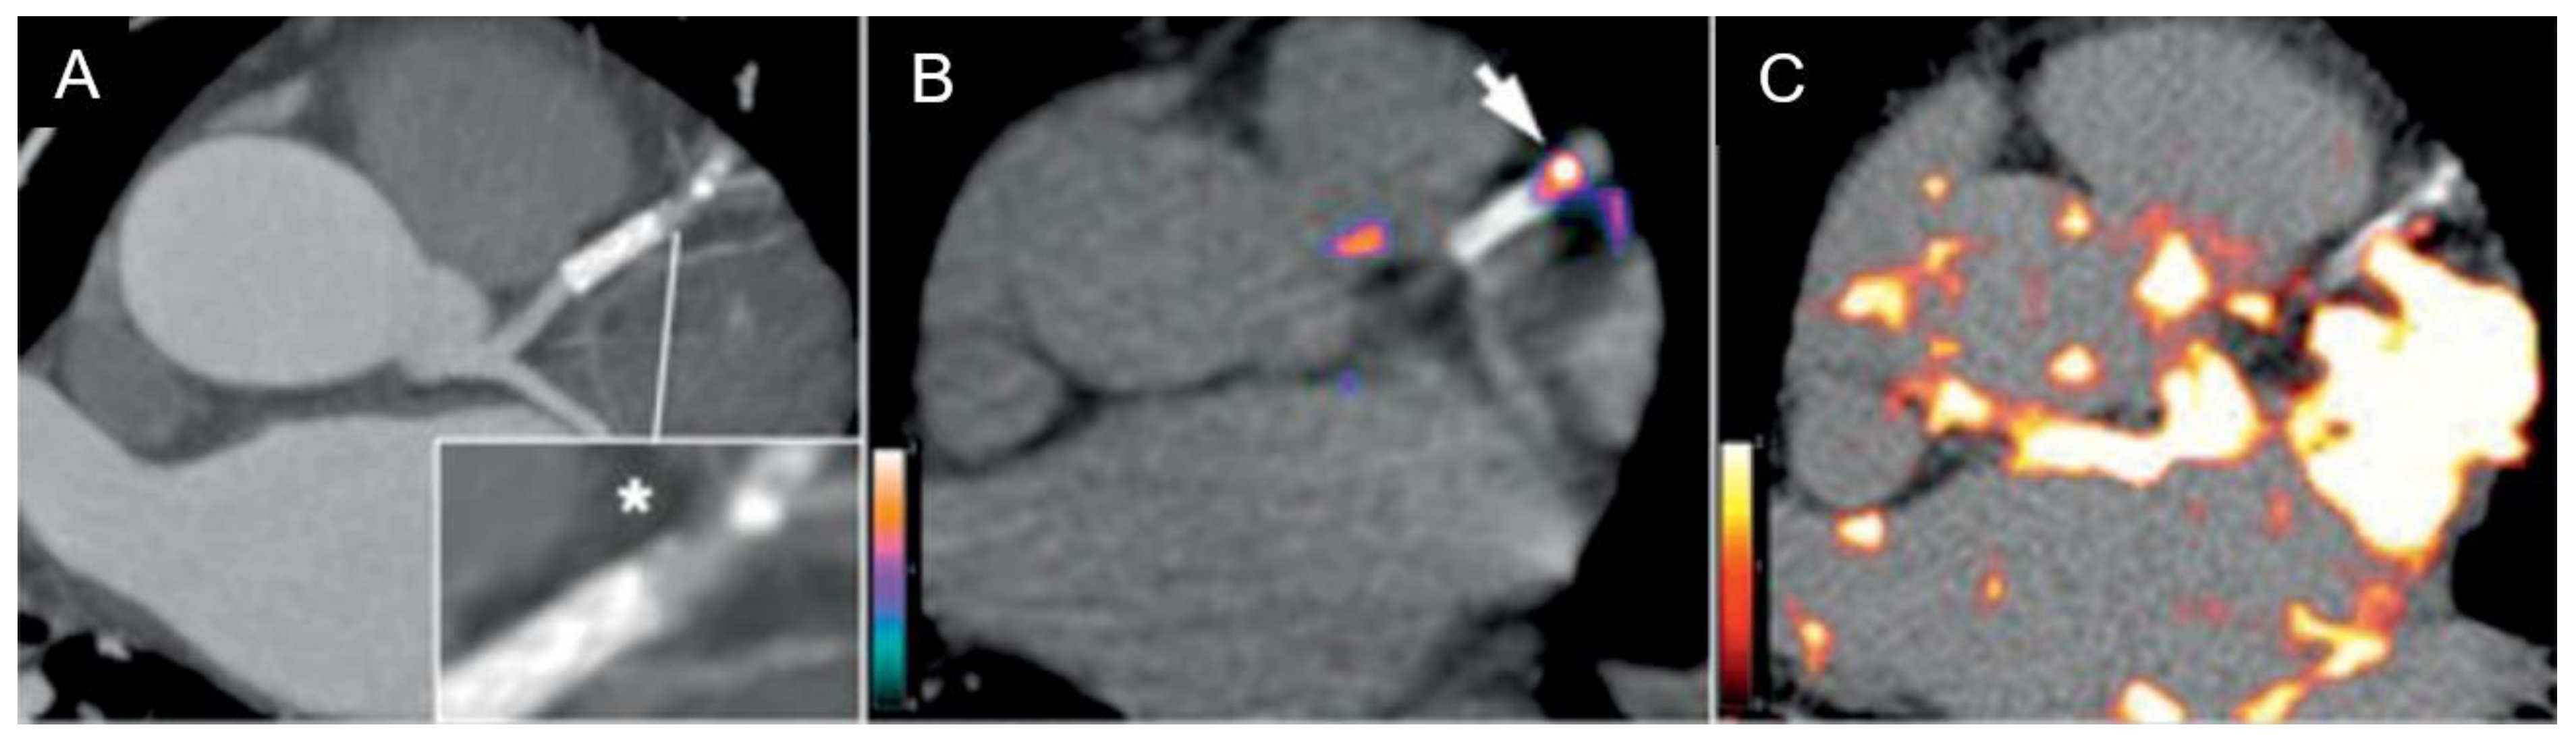

- Dweck, M.R.; Chow, M.W.; Joshi, N.V.; Williams, M.C.; Jones, C.; Fletcher, A.M.; Richardson, H.; White, A.; McKillop, G.; van Beek, E.J.; et al. Coronary arterial 18F-sodium fluoride uptake: A novel marker of plaque biology. J. Am. Coll. Cardiol. 2012, 59, 1539–1548. [Google Scholar] [CrossRef]

- Joshi, N.V.; Vesey, A.T.; Williams, M.C.; Shah, A.S.V.; A Calvert, P.; Craighead, F.H.M.; Yeoh, S.E.; Wallace, W.; Salter, D.; Fletcher, A.M.; et al. 18F-fluoride positron emission tomography for identification of ruptured and high-risk coronary atherosclerotic plaques: A prospective clinical trial. Lancet 2014, 383, 705–713. [Google Scholar] [CrossRef]

- Lee, J.M.; Bang, J.-I.; Koo, B.-K.; Hwang, D.; Park, J.; Zhang, J.; Yaliang, T.; Suh, M.; Paeng, J.C.; Shiono, Y.; et al. Clinical Relevance of 18 F-Sodium Fluoride Positron-Emission Tomography in Noninvasive Identification of High-Risk Plaque in Patients With Coronary Artery Disease. Circ. Cardiovasc. Imaging. 2017, 10. [Google Scholar] [CrossRef]

- Early detection of vulnerable coronary plaques because 18F NaF accumulation in micro-calcification before visibility on CT, allowing earlier intervention. Furthermore, 18F NaF uptake can differentiate between active and indolent calcification in coronary arteries, providing crucial information on plaque activity and potential instability.